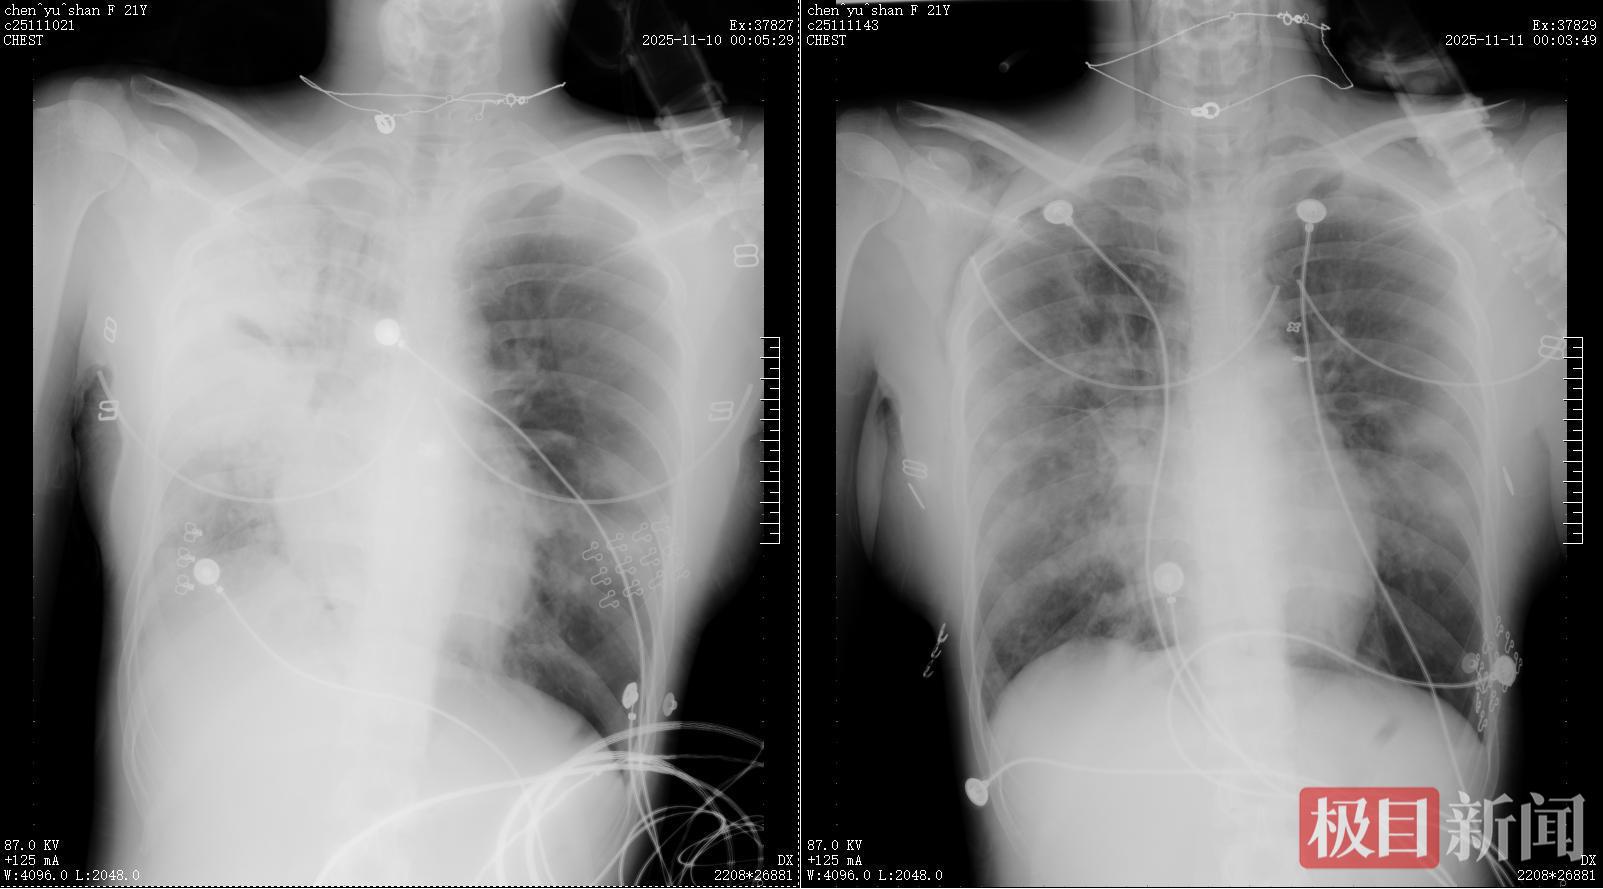

11月11日清晨,赵考昌教授和汤贵良医生查房时,发现小陈在联合呼吸支持下指脉氧饱和度已回升至98%。在评估其身体状态可耐受检查后,团队立即安排床旁支气管镜肺泡灌洗液病原菌检测,精准检出金黄色葡萄球菌、星座链球菌及甲型流感病毒H3N2。明确病因后,医护团队第一时间优化抗生素方案,开展靶向抗感染治疗。当日复查胸片显示,小陈右肺感染较前明显好转,病情迎来重要转机。

治疗前后对比:由此前的“白肺”明显好转